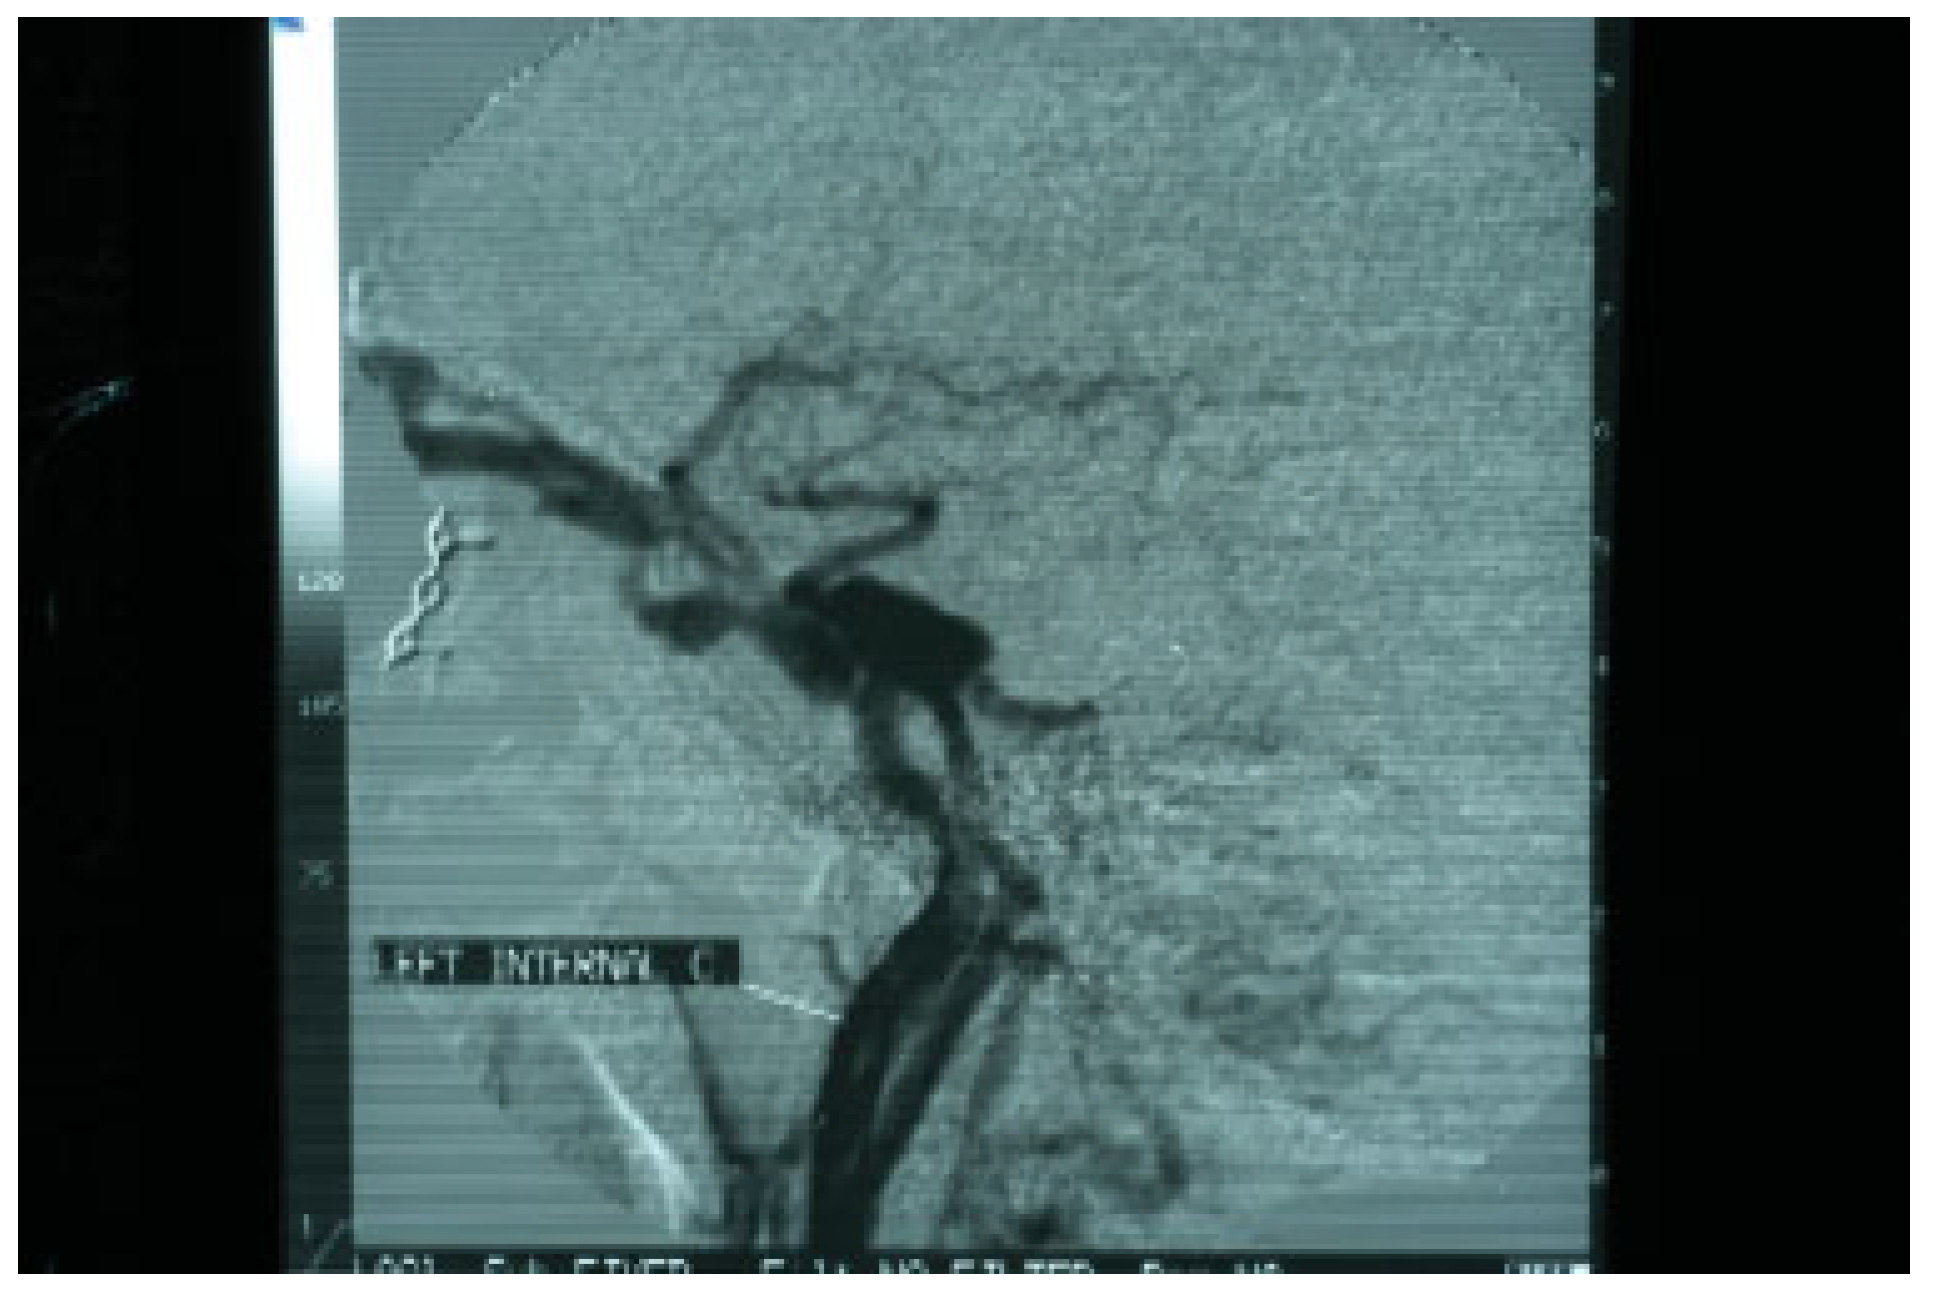

Two days after the removal of the foreign materials, there was a dramatic deterioration of the patient’s clinical presentation with intense ocular pain, worsening of exophthalmos, nausea, and vomiting. The patient also complained of “strange sounds in the cranium like water tapping.” Clinical examination revealed a systolic thrill on palpation of the left eye and a systolic wheeze on auscultation of the left frontal and temporal area. Measurement of intraocular pressure was subsequently performed and an intraocular pressure of 13 mm Hg in the right and 24 mm Hg in the left eye were recorded. Visual acuity was measured 5/6 vision and fundus examination revealed venous dilatation without further pathologic signs. The finding of intensive dilation of the left upper ophthalmic vein in the primary computed tomography was reevaluated and a posttraumatic CCF was suspected and included in the differential diagnosis. A new CT of the left orbit was ordered which revealed a threefold dilation of the cavernous sinus (Figure 4). The digital subtraction angiography (DSA) confirmed the diagnosis of CCF as it revealed a dilation of the cavernous sinus, a blood shunt between the lumen of the internal carotid artery and the cavity of the cavernous sinus, and a dilation of the upper ophthalmic vein (Figure 5).

Figure 4. Computed tomography of the base of the skull illustrating a threefold dilation of the left cavernous sinus.